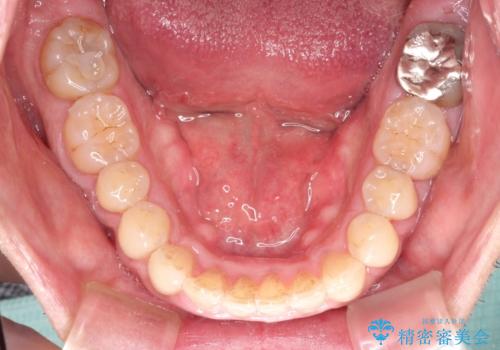

インビザライン invisalign ガタつきを治すマウスピース矯正

- 非抜歯・上顎臼歯遠心移動によるマウスピース矯正を計画した。

ガタつきを取り除くだけであれば非常に簡潔であるマウスピース矯正ですが、奥歯の位置関係の是正や、垂直的な歯の位置のコントロールなどが計画に含まれる場合、治療が難しくなってきます。